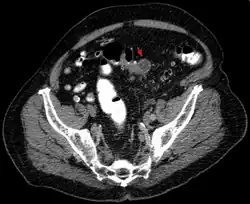

Tomografia komputerowa wykonywana jest z podaniem środka kontrastowego. Typowymi zmianami są symetryczne, zapalne zgrubienie ściany jelita grubego, rozległe nacieki tkanki tłuszczowej okołojelitowej, nagromadzenie płynu w krezce esicy i nastrzyknięcie naczyń w krezce esicy. Czułość badania ocenia się na 95%, swoistość na 35%[24]. Tomografia komputerowa ma również duże znaczenie w rozpoznaniu powikłań jak: ropnie okołojelitowe, stany zapalne otrzewnej, przetoki, i niedrożność jelit.

- Diagnostyka obrazowa uchyłkowatości i powikłań.

Obraz CT Niezmienione uchyłki esicy

Obraz CT Mały ropień w jamie brzusznej spowodowany stanem zapalnym uchyłków

Obraz CT Stan zapalny uchyłków i ropień w jamie brzusznej